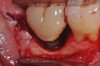

Figure 1

Clinical exposure of a circumferential lesion that demonstrates 3 mm of bone loss. No cement was present, suggesting that the lesion was of bacterial origin. Surface decontamination included citric acid.